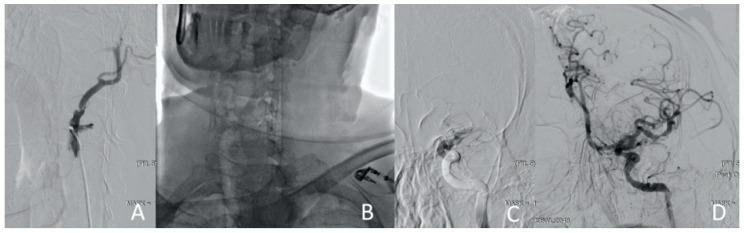

A type A aortic dissection (TAAD) is a dangerous condition requiring emergency surgery. Due to the similarity of the symptoms of cerebral malperfusion in TAAD and the signs of ischemic stroke, a differential diagnosis of these diseases is not always available. Patients with TAAD after cerebral malperfusion can have a neurological deficit. Thrombolysis is performed in this case. It can worsen the patient's condition and increase the risk of mortality and disability. The aim of the study is to evaluate the new approach to restoring cerebral perfusion during aortic dissection. This approach includes endovascular recanalization and carotid stenting.

Two clinical cases of TAAD complicated by cerebral malperfusion are described. The first patient is 73 years old and was admitted as planned to perform transcatheter aortic valve implantation (TAVI) for grade III aortic stenosis. The patient underwent transcatheter aortic valve implantation (TAVI) on the second day after admission. The second patient is 60 years old and was hospitalized by an ambulance with strong hypertension and ischemia. The surgical correction of aortic dissection was postponed until the neurological status assessment in both patients.

The surgery to correct the aorta dissection was deemed inappropriate. The carotid arteries have been reanalyzed, and cerebral perfusion has been restored in a short time in both patients.

Acute bilateral internal carotid occlusion is a potentially fatal TAAD outcome. Emergency endovascular recanalization and carotid stenting may be considered one of the few ways to restore cerebral perfusion.